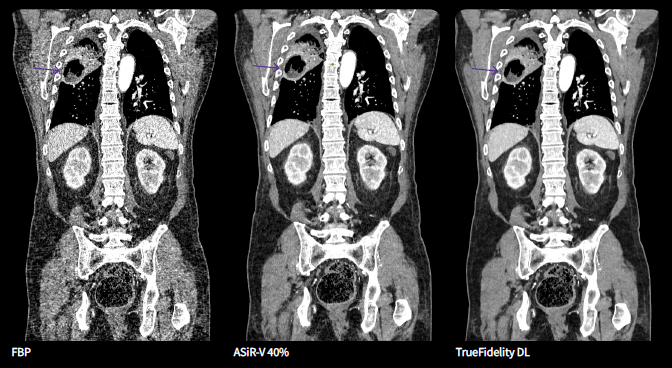

For the growing practice of cardiac CT, GE HealthCare offers TrueFidelity DL with the cardiac kernel, enabling outstanding detail at low doses, with improved visual sharpness for confident reporting and accepted image texture. The value of this AI-powered tool is fully realized when combined with the company’s Revolution Apex platform – which boasts a 0.23 second rotation time for one-beat cardiac imaging – and ECG-less Cardiac solution to acquire cardiac images without the aid of the patients’ ECG signal/trace.

TrueFidelity DL (CT) offers impressive image quality performance[ix], and preferred image sharpness and noise texture,[x] without compromising dose performance. As a result, the technology – which also includes kernels for lung and bone imaging – can improve reading confidence across a wide range of clinical applications such as head, whole body and cardiovascular, for patients of all ages. New this year, TrueFidelity DL is now available on Revolution Ascend platform, Revolution Maxima and to new and existing Smart Subscription customers.

“The sharpness of the images is a breakthrough development in image reconstruction algorithms. We see details that we have never seen before. Abdominal, lung and cardiac imaging benefits most from this technology. I am mainly interested in cardiac and cardiovascular imaging. We found much better image quality, depiction of details, and image sharpness for cardiac valves, sclerotic and soft plaque in cardiac and extracardiac vessels, as well as fewer artifacts around stents and stent-grafts. DECT for pulmonary embolism easily convinced everybody in our department.” — Prof. Klaus Hergan, University Hospital Salzburg, Austria Department of Radiology of the 1200-bed University Hospital Salzburg[xi]

[ix] Image quality comparisons between DLIR and ASiR-V, were evaluated by phantom tests of MTF, SSP, axial NPS, standard deviation of image noise, CT Number accuracy, CNR, and artefact analysis. Additionally, LCD was demonstrated in phantom testing using a model observer with the head and body MITA CT IQ Phantoms (CT191, CT189 The Phantom Laboratory). DLIR and ASiR‐V reconstructions were performed using the same raw data.

[x] As demonstrated in a clinical evaluation consisting of 60 cases and 9 physicians, where each case was reconstructed with both DLIR and ASiR‐V and evaluated by 3 of the physicians. In 100% of the reads, DLIR’s image sharpness was rated the same as or better than ASiR‐V’s. In 91% of the reads, DLIR’s noise texture was rated better than ASiR‐V’s. This rating was based on each individual reader’s preference.